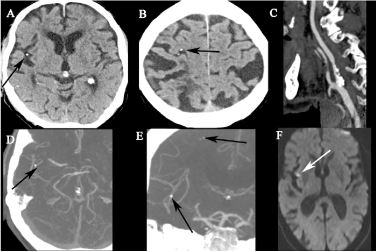

石灰化脳塞栓(calcified cerebral embolism) ・石灰化塞栓子による脳梗塞 ・塞栓源:大動脈弁/僧帽弁石灰化,頸動脈/大動脈弓部等のアテローム性動脈硬化 ・塞栓先:中大脳動脈が最多 ・石灰化塞栓:1-5.5mm,円形-卵円形 ・再発リスクは43-75%と高い(診断と塞栓源指摘は重要) #Rdiag

・石灰化塞栓子による脳梗塞

・塞栓源:大動脈弁/僧帽弁石灰化,頸動脈/大動脈弓部等のアテローム性動脈硬化

・塞栓先:中大脳動脈が最多

・石灰化塞栓:1-5.5mm,円形-卵円形

・再発リスクは43-75%と高い(診断と塞栓源指摘は重要)